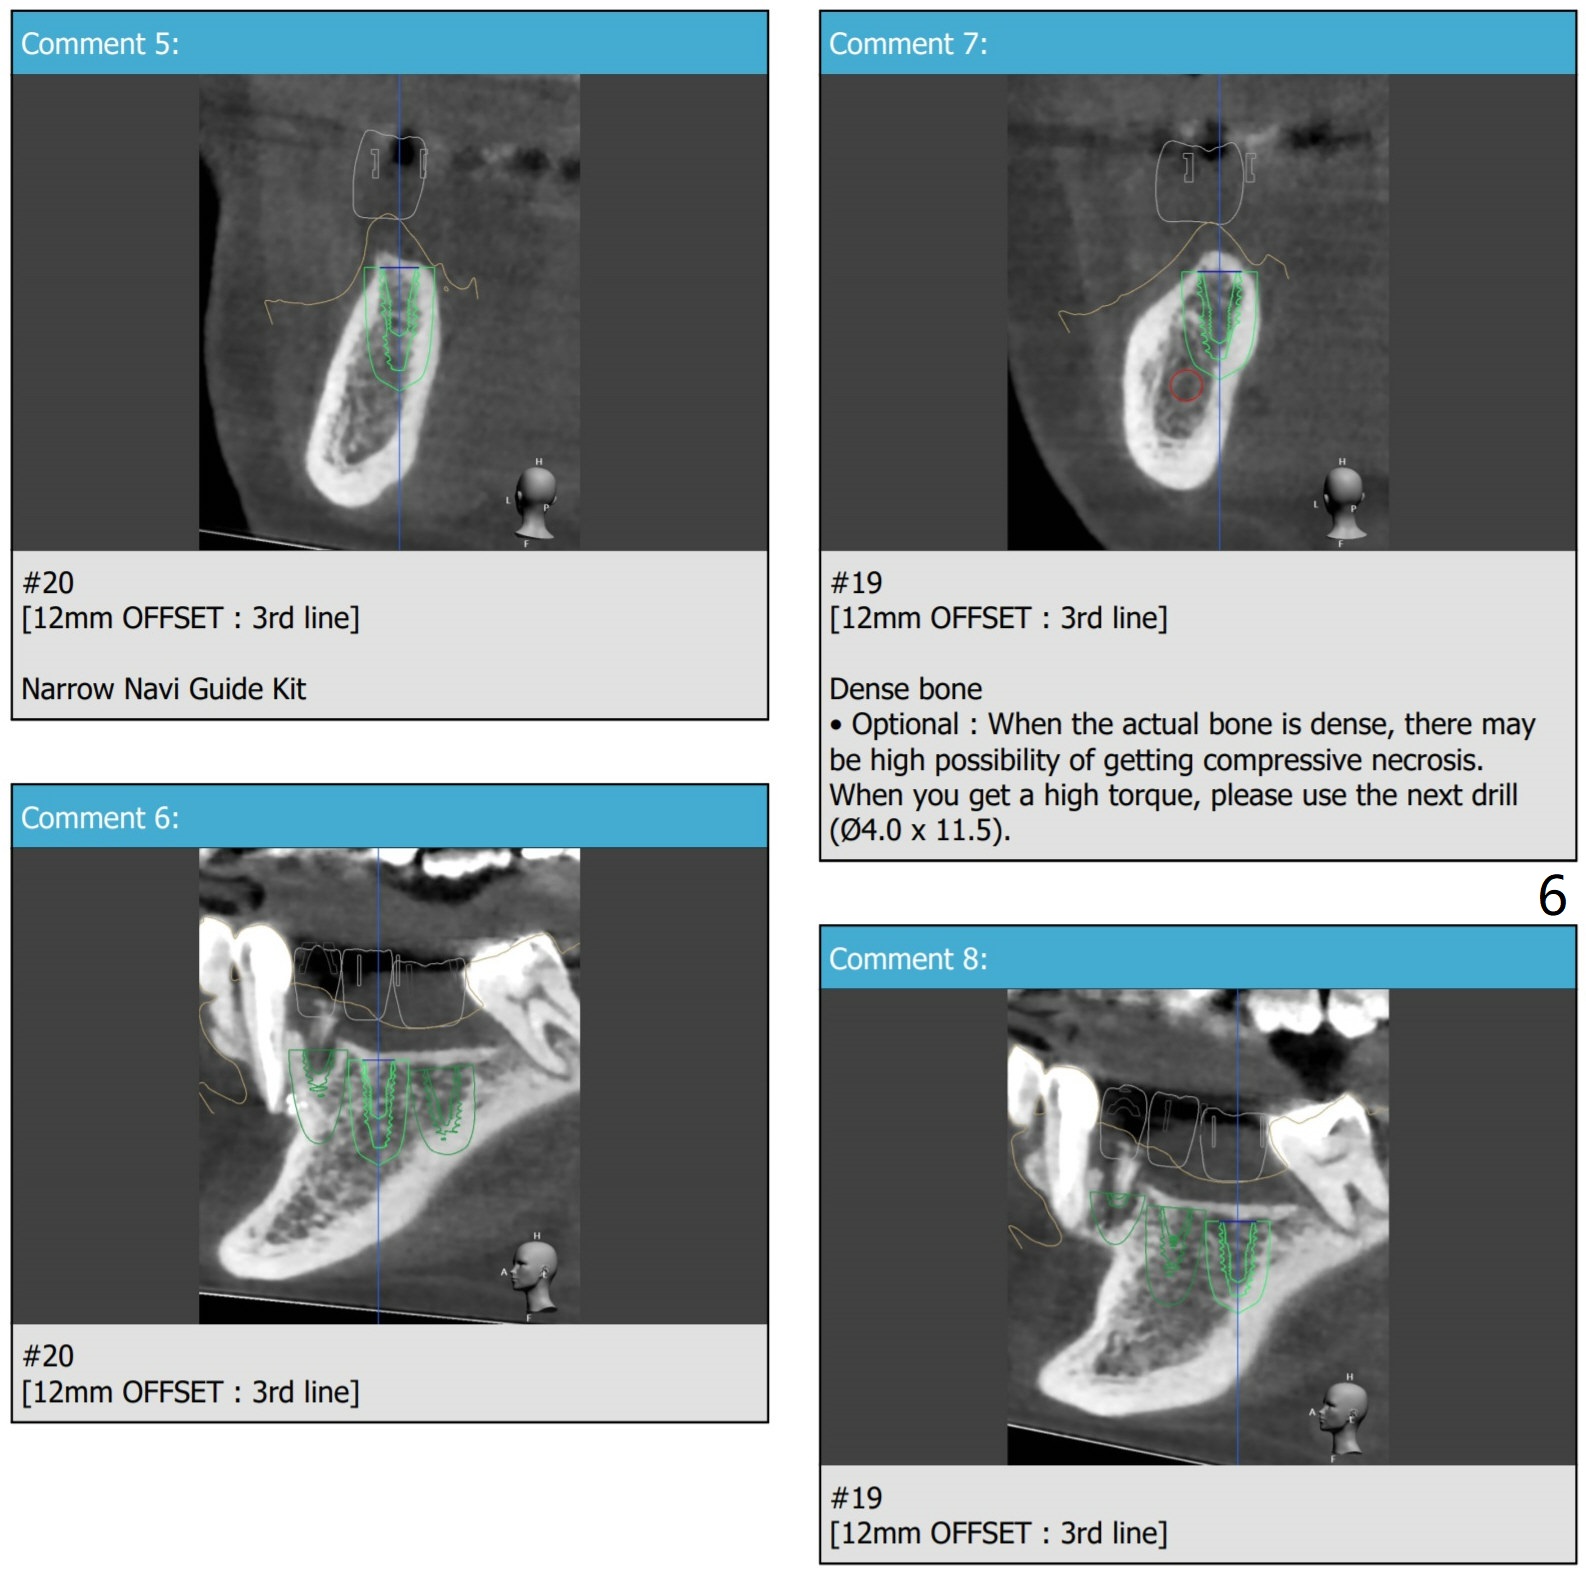

3 Implants In a Row

Yes you can but, I think you'll be able to connect fixture mount on #20 only because there's only one you can use in the narrow naviguide kit.